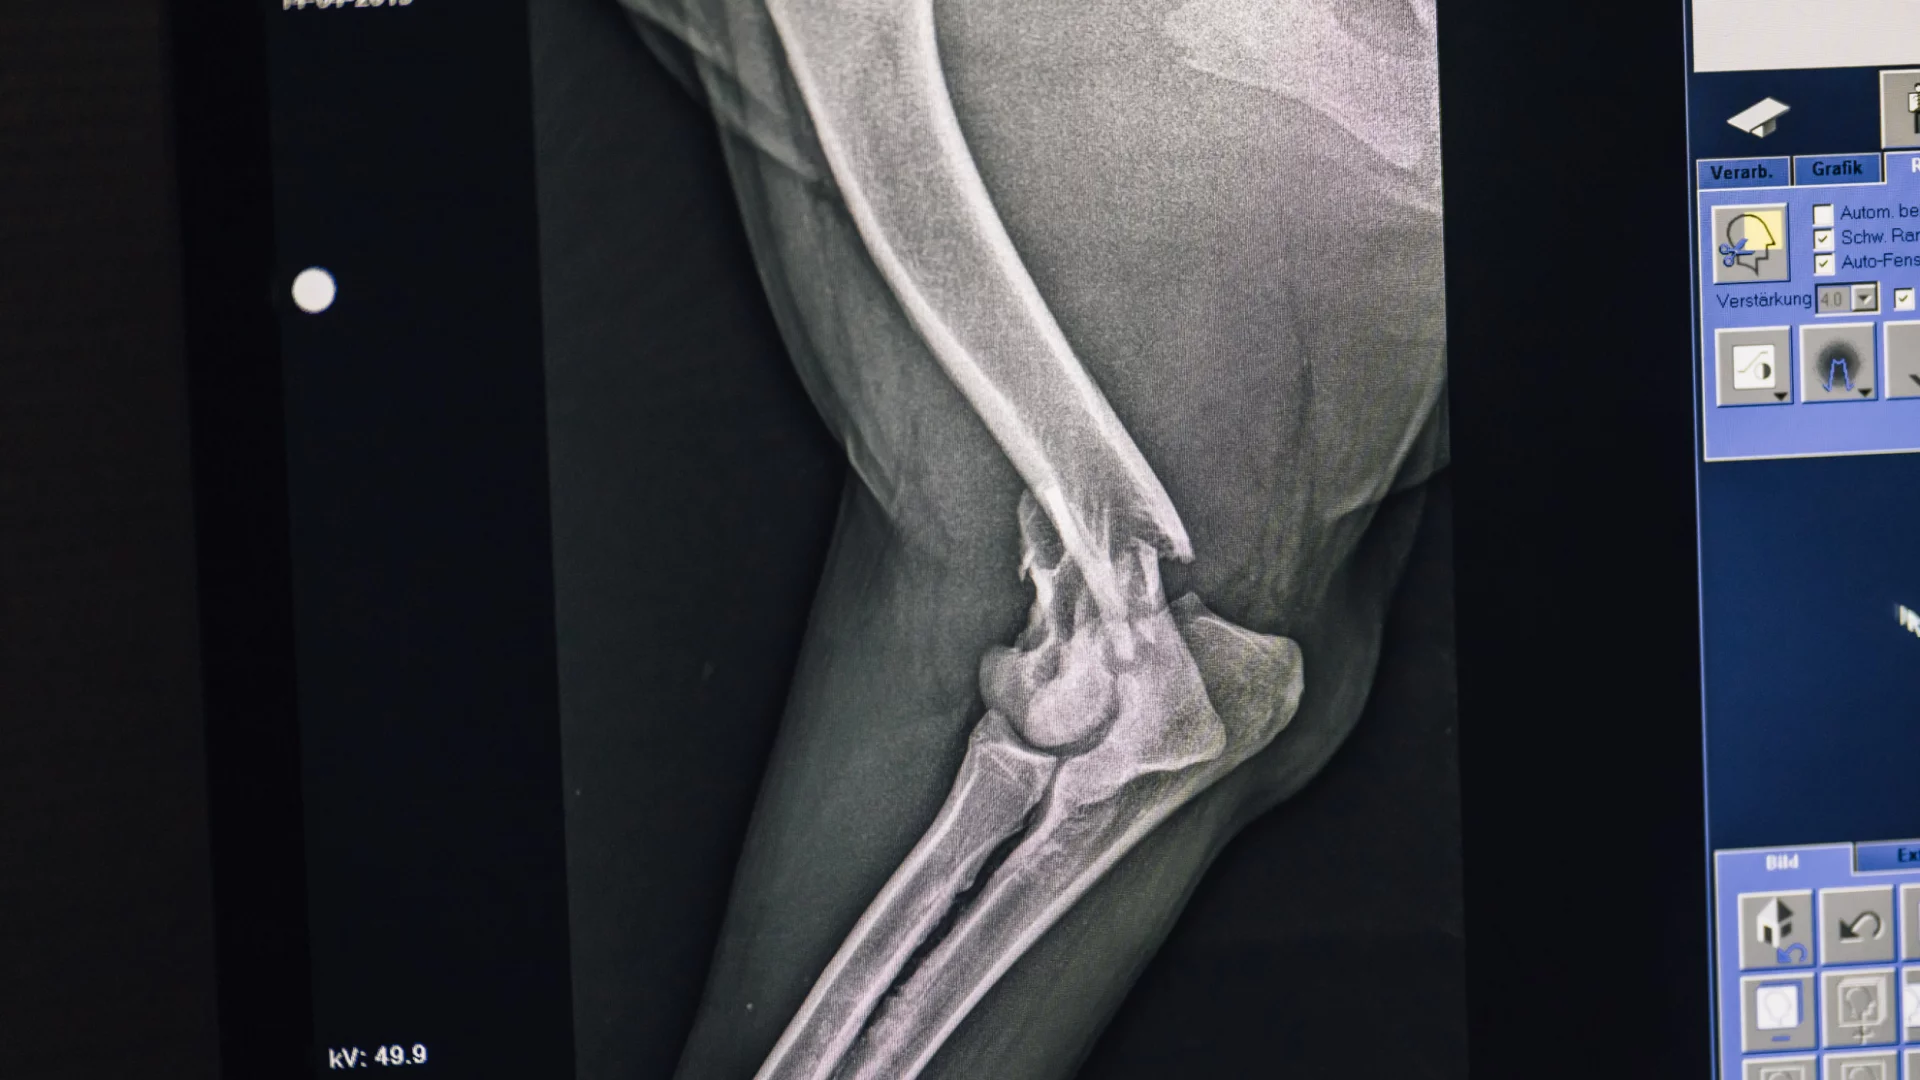

Sichere und schonende Diagnostik mit modernster digitaler Röntgentechnik

Unser digitales Röntgen sorgt strahlungsarm für präzise Aufnahmen von Organen, Skelett und Gebiss